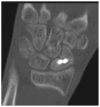

Background: Percutaneous techniques have been described for the treatment of nondisplaced scaphoid fractures, although less information has been reported about outcomes for unstable, displaced fractures. The aim of this study was to evaluate the union and complication rates following manual closed reduction and percutaneous screw placement for a consecutive series of unstable, displaced scaphoid fractures.

Methods: A total of 28 patients (average age, 27 years; 22 male/6 female) were treated for isolated unstable displaced scaphoid waist fractures. Closed reduction and percutaneous headless, compression screw fixation was successfully performed in 14 patients (average age, 32 years; 10 male/4 female), and the remaining 14 patients required open reduction. Patients who underwent percutaneous treatment were followed for radiographic fracture union and clinical outcomes.

Results: Thirteen of 14 fractures (93%) had clinical and radiographic evidence of bone union at an average of 2.8 months postoperatively. Average visual analog pain score at the time of union was 0.9. The average Quick Disability of the Arm, Shoulder, and Hand score at 2.5 years follow-up (range, 1.5-8.3 years) was 9.6 (range, 0.0-27.3). Complications included 1 case of nonunion and 1 case of intraoperative Kirschner wire breakage.

Conclusions: Manual closed reduction followed by percutaneous headless, compression screw fixation was possible in 50% of patients who presented with acute unstable, displaced scaphoid fractures. This technique appears to be a safe and effective method when a manual reduction is possible, and it may offer a less invasive option when compared with a standard open technique.